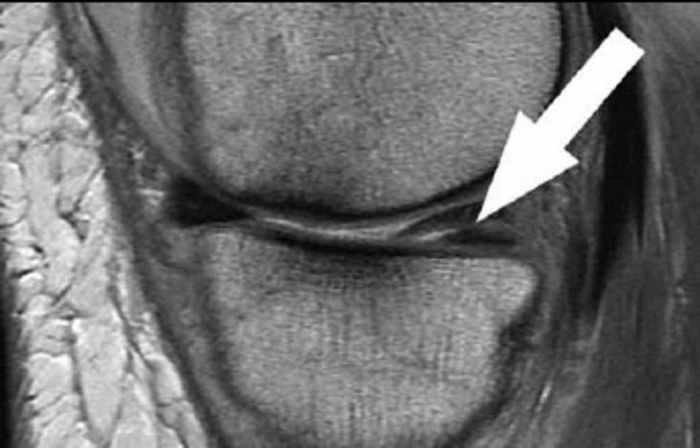

Τη διάγνωση, όμως, όπως και τη θεραπεία που θα ακολουθηθεί, θα την καθορίσει ο ορθοπαιδικός χειρουργός μετά από κλινική εξέταση και μαγνητική τομογραφία της άρθρωσης, ώστε να εντοπιστεί η ακριβής έκταση της ρήξης αλλά και τυχόν συνοδές βλάβες (στους αθλητές, για παράδειγμα, πολλές φορές η ρήξη μηνίσκου συνυπάρχει με την ρήξη του πρόσθιου χιαστού).

Στα παραπάνω ευρήματα θα συνεκτιμηθεί και η ηλικία του ασθενούς όπως και το εύρος των δραστηριοτήτων του, ώστε να έχουμε την καλύτερη εξατομικευμένη αντιμετώπιση του προβλήματος.